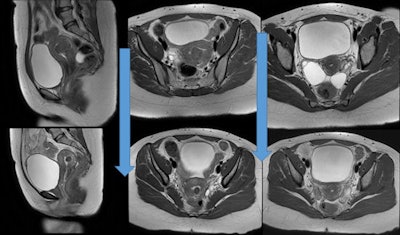

خلال عملية معالجة الورم الليفي الرحمي بالقثطرة.

تتميز معالجة الأورام الليفية الرحمية عن طريق القثطرة بأنها أبسط و بأن نسبة المشاكل والاختلاطات أقل مقارنة بالاستئصال الجراحي حيث يتم اجراء القسطرة بدون تخدير عام و ياخذ الاجراء 45 دقيقة و تخرج المريضة من المشفى في نفس اليوم.